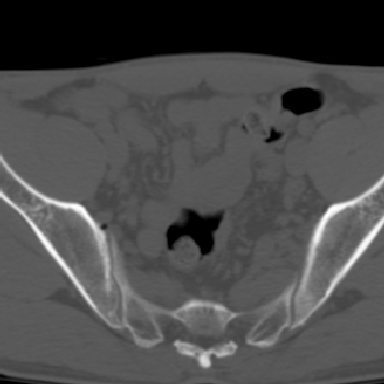

m 30 腰背部不适半年; 清晨时僵硬; 活动症状有所改善

双侧骶髂关节下2/3关节面模糊,毛糙,可见小囊状骨质破坏区.支持强直性脊柱炎.

强直性脊柱炎的早期改变!不仅表现为双侧骶髂关节,第5腰椎与骶椎间的关节突关节也有类似改变。

双侧骶髂关节下2/3关节面模糊,毛糙,髂骨侧可见小囊状骨质破坏区,骶髂关节间隙增宽(软骨破坏期)。支持早期强直性脊柱炎。

双侧骶髂关节下2/3关节面模糊、毛糙,可见小囊状骨质破坏区,呈虫咬状改变,周围可见增生硬化.支持强直性脊柱炎早期表现.

双侧骶髂关节髂骨面硬化,毛糙,小囊变,属于早期强直性脊柱炎